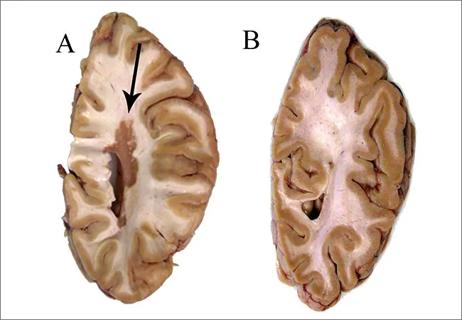

Myelocortical Multiple Sclerosis: Neurodegeneration Without White Matter Demyelination

Discovery of new MS subtype suggests that the axon itself may be primary site of injury